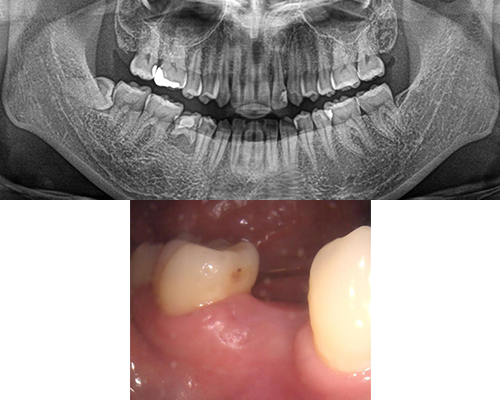

| 施術内容 | 前歯は虫歯や歯の動揺が大きく、奥歯も虫歯や歯根破折のため保存困難。左上1本以外抜歯し、骨が足りない部位は骨増生を行いインプラント治療へ。通常の入れ歯と違いインプラントを固定源とするため、安定性がかなり高いです。(治療期間中は入れ歯を使用) |

|---|---|

| 治療期間 | 約1年半(抜歯後治癒期間含) |

| 治療費 | 約280万円(プラスチック前装冠) |

| 副作用・リスク | インプラント治療は手術を伴います。腫れや痛みが少なくなるよう努力をしておりますが、多少の腫れや痛みが出ます。しかし、痛み止めで抑えられる程度ですのでご安心ください。 |

※表示は全て税込表示です。